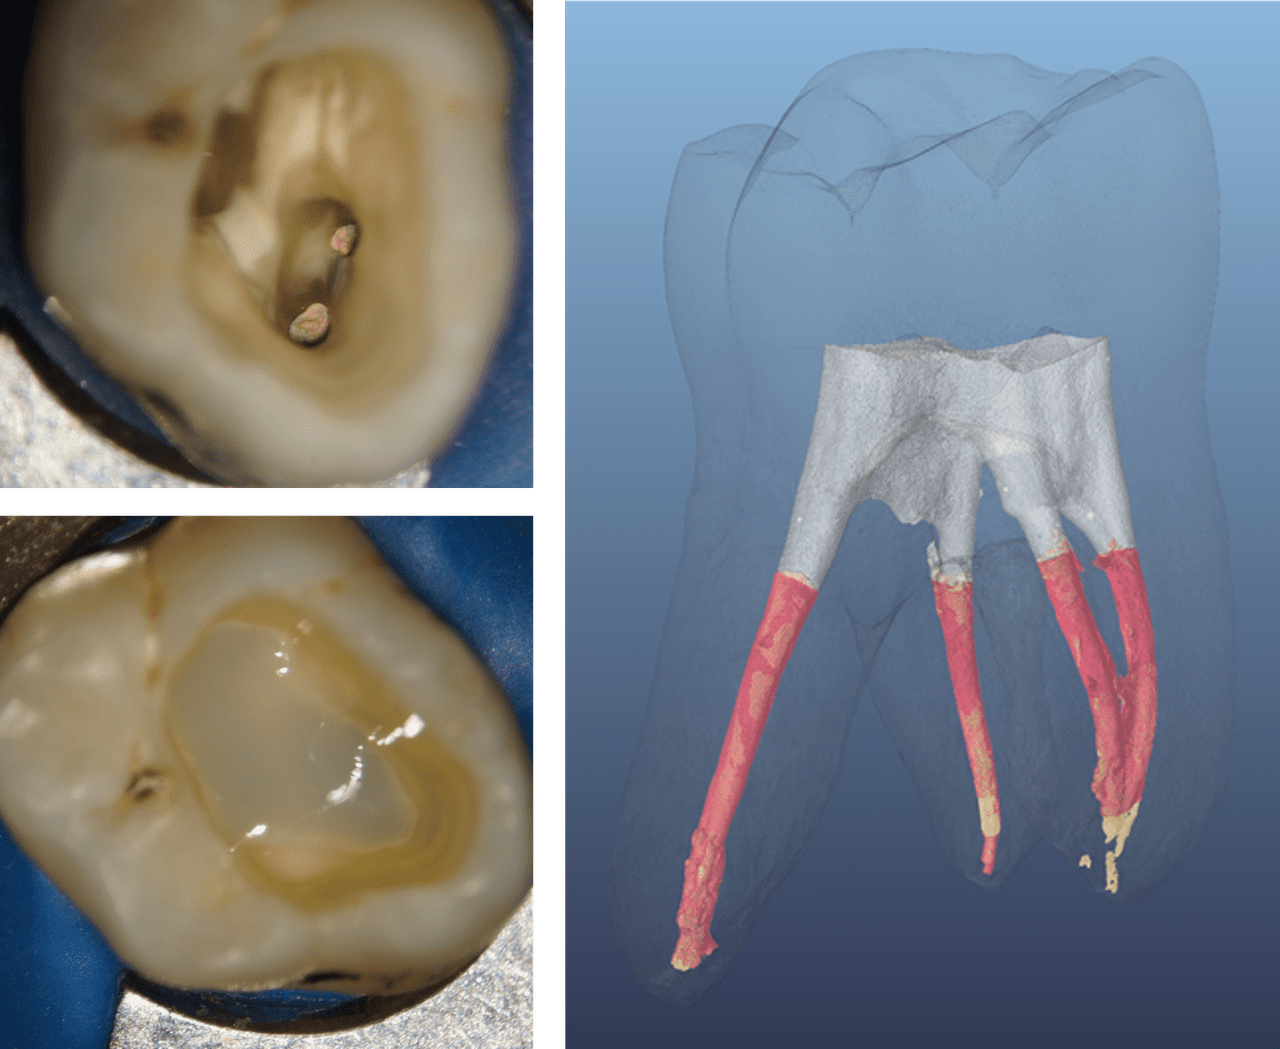

This conclusion finds support in several other reviews and retrospective studies7,8, leading to the conclusion by Atlas aet al. that “[…] in ETT [endodontically treated teeth] with three or four coronal walls left, that is, at least one marginal ridge remaining, and no undermined cavity walls, direct adhesive restoration may be considered as an alternative to cuspal coverage.”5 Figure 2 provides a clinical example of both a Class I and II cavity in endodontically treated teeth, that are matching these criteria, allowing dental practitioners to place a less invasive and more cost effective direct restoration.

Figure 2: Endodontically treated posterior teeth with four and three coronal walls, and barely undermined residual tooth structure before and after direct restoration

(Courtesy of Dr. Marcus Holzmeier, Germany)